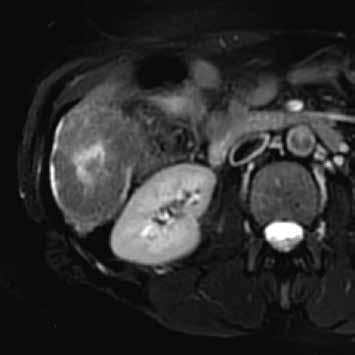

Zánětlivý HCA se v arteriální fázi homogenně sytí, v portovenózní fázi nedochází k vymývání kontrastní látky (obr. 3, 4). Při MR vyšetření můžeme zachytit „atoll sign“, tedy hyperintenzní lem kolem adenomu (obr. 5). Vyskytuje se postkontrastně až ve 25 % případů. V hepatobiliární fázi je tento adenom až ve 30 % hyperintenzní. Výrazné T2 hyperintenzity spojené s přetrvávajícím sycením mají senzitivitu 85–88 % a specificitu 87–100 % pro I-HCA.

HCA inaktivovaný HNF-1α obsahuje tuk, má proto nízký signál na všech sekvencích se saturací = „pseudo washout“, pseudoabsence sycení. V arteriální fázi se výrazně sytí, ale v portální a portovenózní fázi se většinou vymývá. V pozdní fázi je po podání specifické kontrastní látky hypointenzní (obr. 6–10).

HCA mutovaný β-kateninem mívá spíše heterogenní sycení, objevuje se u něho vymývání kontrastu a můžeme detekovat pouzdro. Je u něho tedy větší riziko záměny za HCC (obr. 11–18).